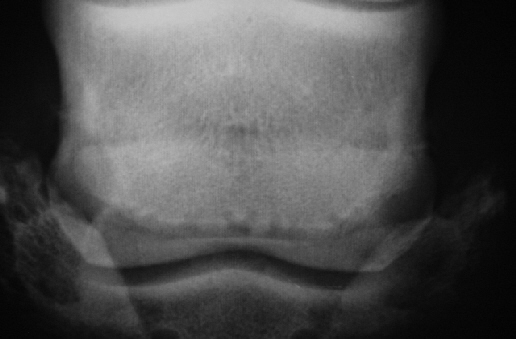

Hufrolle006202

Bei diesem Beispiel liegt eine große Zahl zum Teil schlecht abgegrenzter , zum Teil kolbiger Kanäle vor. Die Kontur des Strahlbeines ist unregelmäßig und konkav mit Doppellinie. In der linken Hälfte ist die Knochenstruktur weniger dicht (A). Dies sind eigentlich Veränderungen der Kategorie III in ihrer Summe aber bis Kategorie IV bzw. Grad 3.